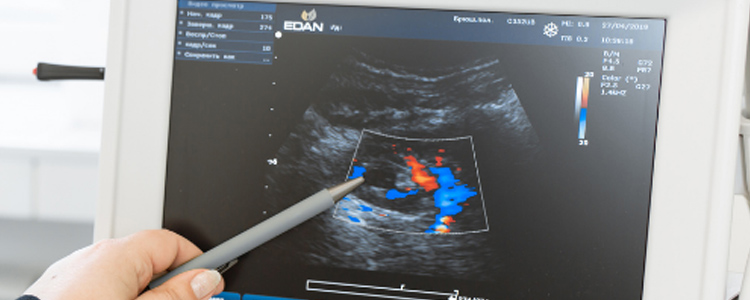

Ultra Sound Scan

Ultra sound scan also known as Ultrasonography is an imaging modality using ultrasonic sound waves which bears a frequency above 20,000 Hertz. It enables the sonologist to visualize the internal organs and the structural and functional status can be defined. Ultrasound scans are noninvasive and do not posess any harmful radiation. As low-power sound waves are used, the method is regarded to be much more safe.

Common reasons for using this test is to investigate a person's abdominal and pelvic organs, musculoskeletal and vascular systems, and to monitor fetal development during pregnancy. It can also be used to diagnose issues in the liver, heart, kidney, or abdomen. These scans might also help to perform certain types of biopsies.